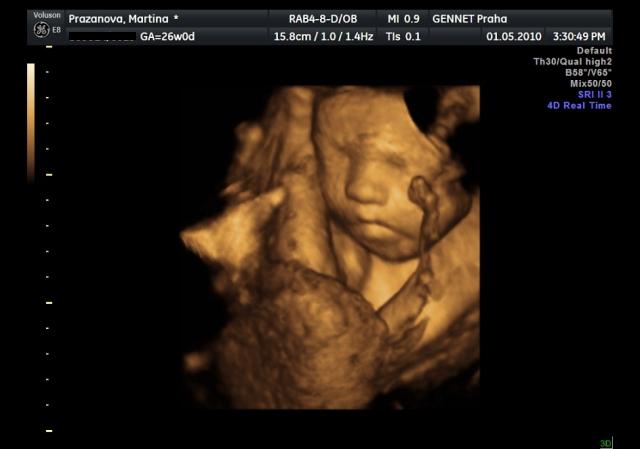

Už se nemůžeme dočkat 1.5....jdeme na 4D UTZ, tak doufám, že se nám ten náš klučík ukáže v plné své kráse 🙂))